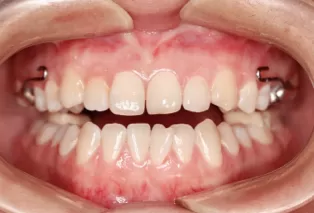

Intraoral photos after treatment